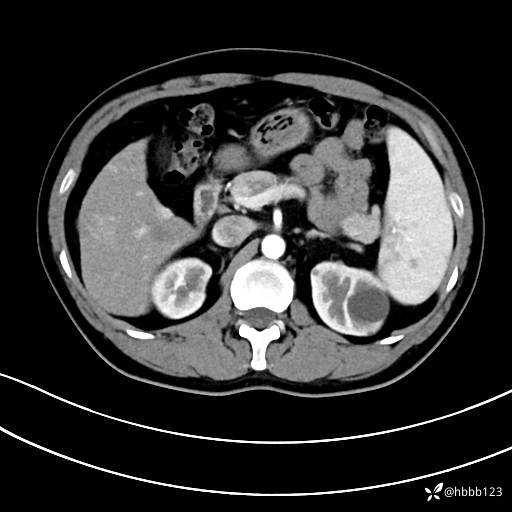

延迟期: